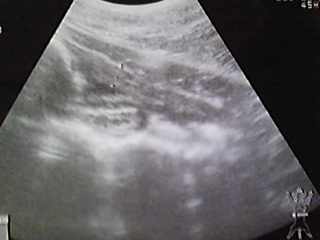

④ 11月16日

別の写真ょり、一番下の一番横長の

白=腸

その上の腸以外の白はストラバイトの可能性

本日のエコー写真は持ち帰りました

見ての通り、ぉシッコ漏らした時に

全部を出し切ってしまったヤツ

今回は尿採取をし、検査をする事が

出来ませんでした。。。

依って、写真や漏らしたシッコでゎ

膀胱炎は治っているだろうとの予測

ストラバイトについては

再び来週・・・11月22日、又は24日に

病院で検査になりました